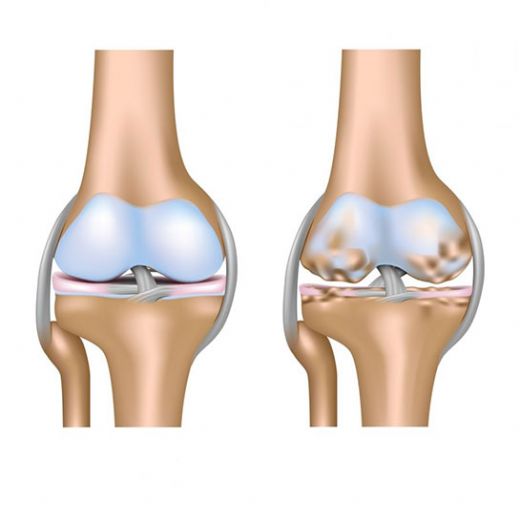

Kıkırdak Doku Çeşitleri Kıkırdak doku, bağ dokuları arasında yer alan, esnek ve dayanıklı bir yapıya sahip olan dokulardır. Farklı türleri ve işlevleri, vücudun çeşitli bölgelerinde önemli roller üstlenmektedir. Bu makalede, kıkırdak dokunun çeşitleri ve özellikleri detaylı bir şekilde ele alınacaktır. Kıkırdak Doku Türleri Kıkırdak doku üç ana türde sınıflandırılmaktadır: hyalin kıkırdak, elastik kıkırdak ve fibröz kıkırdak. Her bir tür, farklı yapısal özelliklere ve işlevsel amaçlara sahiptir.

Kıkırdak Doku ve Hastalıklar Kıkırdak dokunun sağlık durumu, birçok hastalığın gelişiminde önemli bir rol oynamaktadır. Osteoartrit gibi dejeneratif hastalıklar, kıkırdak dokusunun bozulmasıyla ilişkilidir. Ayrıca, kıkırdak dokunun yaralanmaları, spor yaralanmaları ve travmalar sonucunda meydana gelebilmektedir. Kıkırdak Doku Araştırmaları ve Gelecek Perspektifleri Günümüzde kıkırdak doku araştırmaları, doku mühendisliği ve yenileyici tıp alanında yoğunlaşmaktadır. Kıkırdak hasarını onarmak veya yeniden oluşturmak amacıyla hücresel tedavi yöntemleri ve biyomühendislik uygulamaları geliştirilmektedir. Bu alandaki ilerlemeler, kıkırdak ile ilgili hastalıkların tedavisinde önemli yenilikler getirebilir. Sonuç olarak, kıkırdak doku, vücutta önemli bir rol oynamakta olup, farklı türleriyle birlikte çeşitli işlevler üstlenmektedir. Bu yapıların sağlığı, genel sağlık durumu üzerinde önemli bir etkiye sahiptir ve araştırmalar bu alanda devam etmektedir. |

Kıkırdak dokunun kendini yenileme özelliğinin az olması, maalesef eklem sağlığı açısından ciddi sorunlar yaratabilir. Kıkırdak dokusu, eklemlerimizin düzgün hareket etmesini sağlar ve bu dokunun zarar görmesi, ağrı, sertlik ve hareket kısıtlılığı gibi problemlere yol açabilir.